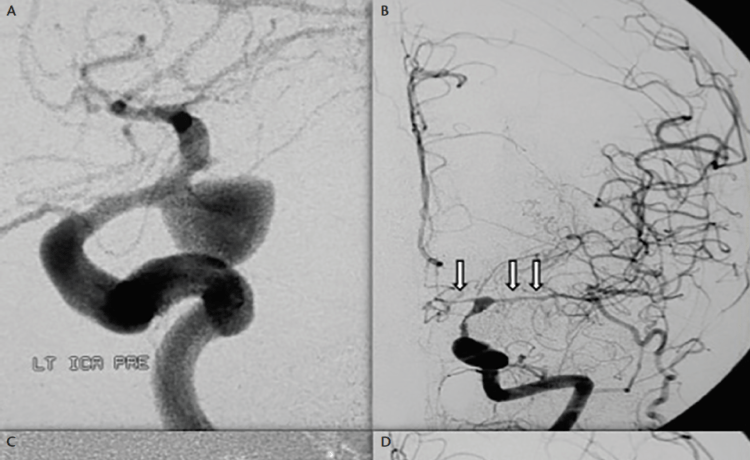

Also known as cerebral vasospasm, usually follows days after another disease affecting the brain known as a subarachnoid haemorrhage (SAH). SAH is a type of stroke that happens when the blood vessels on the surface of the brain breaks. The bleeding occurs in the space below one of the thin layers that cover and protect the brain. SAH is usually caused by a burst blood vessel in the brain, typically a ruptured brain aneurysm. Brain aneurysm is a weak or thin spot on a blood vessel, usually artery, that balloons or bulges due to the blood that has filled in it. SAH may also occur after a trauma to the head but it is rather rare to be causing vasospasm. SAH is the most dangerous type of stroke because it is able to lead a person to coma or a person being paralyzed. Some might survive a SAH but then will have cerebral vasospasm again and put a person’s life in danger for the second time.

Imaging test is usually done by a doctor to look for the SAH sign or other causes leading to the cerebral vasospasm. Imaging tests such as cerebral angiography, transcranial doppler ultrasound, CT or MRI scan are among the imaging tests commonly asked by doctors to help diagnose SAH and vasospasm.